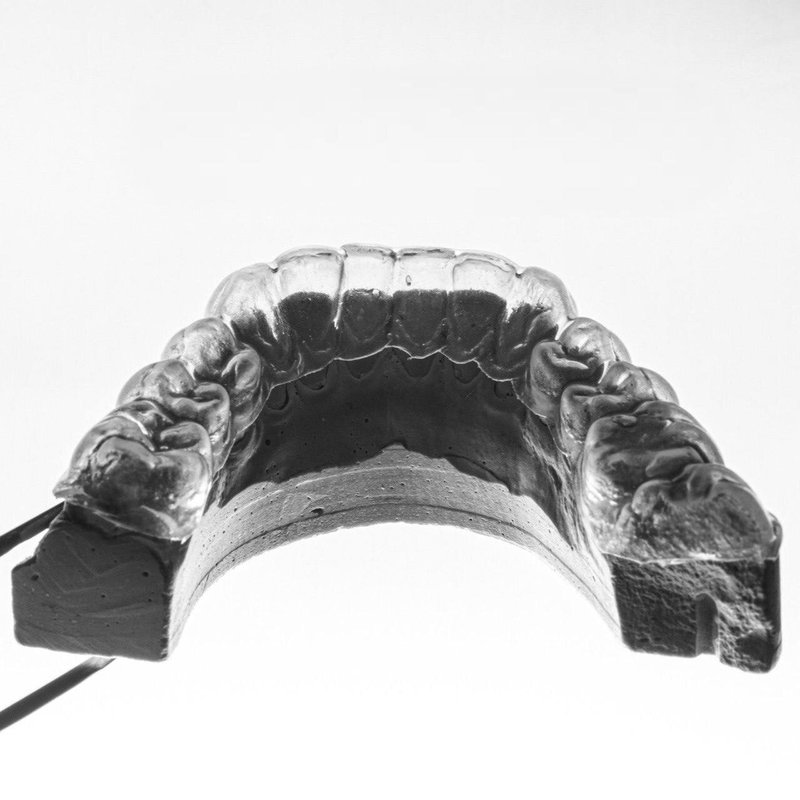

Фотогалерея

Выполняет детальные обследование и диагностику полости рта с помощью компьютерных технологий. Определяет причину нарушений и наиболее подходящий способ протезирования для восстановления нарушенной зубочелюстной системы. Разрабатывает план лечения.

- Выполняет детальное обследование и диагностику полости рта с помощью компьютерных технологий.

- Определяет причину нарушений и наиболее подходящий способ протезирования для восстановления нарушенной зубочелюстной системы.